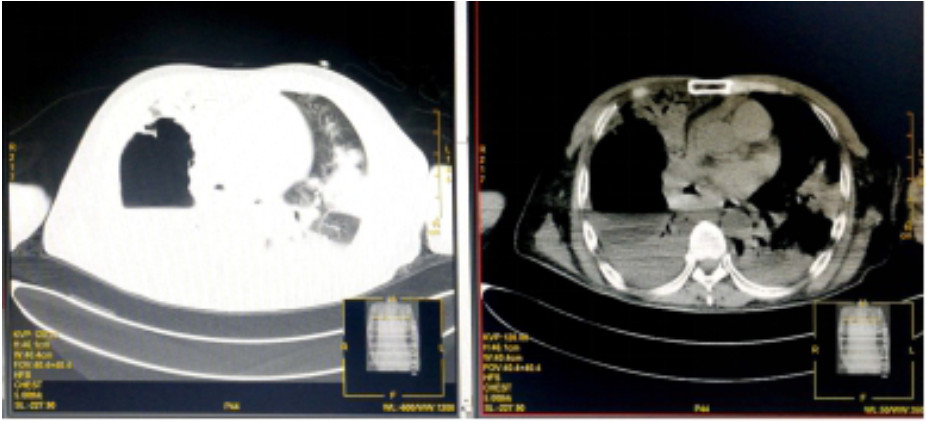

入院诊断“社区获得性肺炎”。予无创呼吸机支持(FiO2 75%),经验性予以美罗培南静脉泵入1.0 g 2次/d、磷酸奥司他韦口服75 mg 2次/d、莫西沙星静脉滴注0.4 g 1次/d。入科后治疗4 h仍无尿,且呼吸困难进行性加重,血氧饱和度进行性下降,氧合指数109 mmHg,予以经口气管插管接呼吸机辅助通气及连续性血液净化等治疗。机械通气后,吸出大量灰褐色痰,且病情进展快,短时间无法脱机拔管,12月17日气管切开。12月17日复查血常规:血白细胞2.49×109/L,中性粒细胞百分比0.925,血红蛋白70 g/L,血小板62×109/L。停用莫西沙星改用利奈唑胺0.6 g静脉滴注2次/d。12月19日胸部CT示,⑴双肺散在多发感染性病变,右侧为著;⑵右肺空腔伴气液平;⑶右侧胸腔积液(图 2)。12月19日血白细胞3.7×109/L,中性粒细胞百分比0.882,淋巴细胞百分比0.098,血红蛋白78 g/L,血小板115×109/L,入科后立即送检的血、痰培养回报均阴性。12月20日肺泡灌洗液病理回报镜下见炎症细胞、吞噬细胞及菌丝样物,未发现恶性细胞(图 3)。12月21日痰宏基因组学检测回报:肺炎链球菌(序列数113 916)、屎肠球菌(序列数1 307)、铜绿假单胞菌(序列数16)。12月20日及24日肺泡灌洗液、血培养均回报为屎肠球菌,药敏试验结果示,对氨苄青霉素、环丙沙星、红霉素、庆大霉素、青霉素耐药;对替考拉宁、替加环素、利奈唑胺、万古霉素、奎奴普丁/达福普丁敏感。继续利奈唑胺600 mg 2次/d,总疗程62 d。治疗期间血红蛋白在66~91 g/L,血小板均在(100~300)×109/L。12月26日CT引导下经皮肺组织穿刺术,并送检病理细胞学及组织培养,结果显示符合炎症性病变改变,病原学阴性。2020年1月9日脱离呼吸机,1月14日转入普通病房,1月23日拔出气管切开套管,2020年2月13日复查胸部CT病灶有所吸收(图 4),2月24日好转出院。出院半年后电话随访,当地医院复查胸部CT示病灶较前明显吸收,已经正常工作。

图 2 患者2019年12月19日胸部CT结果(双肺散在多发感染性病变,右侧为著;右肺空洞伴气液平面;右侧胸腔积液)